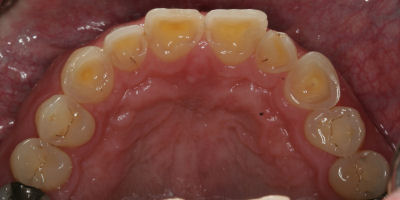

Opening Bite

Repair Worn Teeth